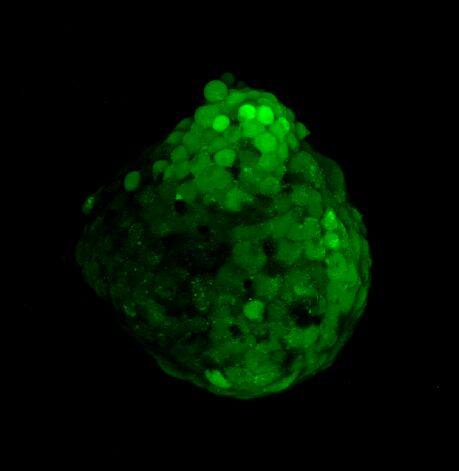

为了生成 3D 球体,将 NCI-H460 细胞(源自非小细胞肺癌)以两种不同的密度接种在超低吸附培养板中:3×103 个细胞/孔或 700 个细胞/孔。在直径分别达到约 400-500 或 150-200 um 后,用细胞毒素剂处理球体 6 天。通过使用钙黄绿素 AM 和碘化丙啶 (PI) 的活/死染色来观察和评估药物的效果。钙黄绿素 AM 是一种细胞渗透性染料,用于测定细胞活性。非荧光钙黄绿素 AM 在活细胞中被细胞内酯酶水解后转化为(绿色)荧光钙黄绿素。PI 是一种红色荧光核染色剂,通常用于检测死亡细胞,因为它不能进入完整的活细胞。最后,使用 Hoechst 染料将细胞核染成蓝色。

我们采用 CrestOptics X-Light V3 转盘共聚焦结合 Prime BSI 相机(Photometrics,像素尺寸 6.5 um)进行采集。我们比较了使用 20 倍空气物镜(CFI Plan Apo Lambda,尼康,0.7 NA 和 1mm WD)和 25 倍硅油物镜(CFI Plan Apo Lambda S,尼康,1.05 NA 和 0.55 mm WD)进行的采集。在图 A 中,我们展示了从总共 150 um 的 Z 堆栈中获得的最大强度投影 (MIP) 图像;特别是,使用 20 倍空气物镜和 25 倍硅油物镜获得了相同的球体。图 B 显示了使用两种物镜获得的 3D 球体同一区域的放大。

为了更好地理解 3D 细胞组织,在图 C 中,我们展示了使用两种物镜获得的同一球体的体积视图(120 um 厚),甚至在 3D 肿瘤球体的更深区域也能看到染色。最后,在 图 D 中,显示了使用 25 倍硅油物镜获得的整个球体的 3D 电影特效。

使用 20 倍空气物镜和使用 25 倍硅油物镜获得的图像之间的比较(图 A、B 和 C)突出了基于生物应用的透镜选择的重要性。从 20 倍到 25 倍的转换导致分辨率提高(基于 25 倍的 NA 大于 20 倍 NA),这当然会影响图像质量,并且还会导致光折射减少。事实上,浸油通过用更高折射率的介质代替透镜和盖玻片之间的空气间隙,大大提高了显微镜的分辨率,从而减少了光的折射。

在 3D 成像中,样品的折射率与其浸没介质的折射率相匹配对于深层组织观察至关重要。硅酮浸油非常适合透过厚厚的生物样本进行成像;它与细胞和封固剂的折射率非常吻合,与使用普通 20 倍空气物镜获得的图像相比,减少了球面像差,产生了更亮、分辨率更高的图像。

图 C:使用 20 倍空气物镜(左)和 25 倍硅油物镜(右)获得的球体的 3D 体积视图。活细胞用钙黄绿素(绿色)标记,死细胞用 PI(红色)标记。细胞核用 Hoechst(蓝色)染色。沿 Z 轴的比例尺:120 um。这些图像是使用 CrestOptics X-Light V3 转盘获取的。

图 D:使用 25 倍硅油物镜获得的 3D 球体的 3D 电影特效。活细胞用钙黄绿素(绿色)标记,死细胞用 PI(红色)标记。细胞核用 Hoechst(蓝色)染色。150 um 厚。此图像是使用 CrestOptics X-Light V3 转盘获取的。